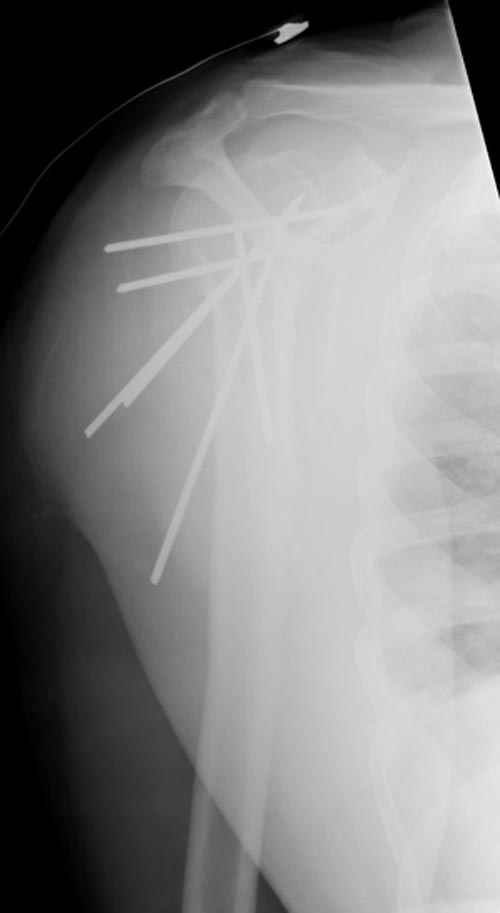

Пока я пользуюсь методикой принятой у нас (методика Сиэтла), также перкутанный спицевой метод, только сцицы 2.8 мм с резбой на конце.

Здесь случай перелома-вывиха плеча, больному 56 лет, после "дважды" закрытой неудачной репозиции, опять же ургентно взяли в операционную, после полного общего обезболивания попытались сделать репозицию, и фиксацию провели спицами.

Больной находился в повязке, примерно напоминяющей косыночную, рекомендованы движения в локтевом суставе и маятниковые движения в плече, спицы удалены в три недели (были случаи миграции)

Больной амбулаторный, предупрежден на случай осложнения АВН головки.